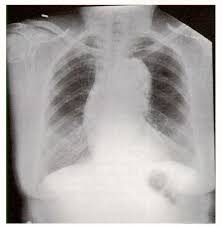

28. Choice B is the correct answer. This patient has a widened mediastinum. Marfan's as well as all connective tissue diseases are risk factors for aneurysms. The patient also so should have ECHO's periodically but emergently he needs an CTA of the Chest. Nitroglycerin would not be helpful. Heparin may be detrimental because he could be dissecting.

28. Your patient is a 28 year old patient with Marfan's Syndrome that presents with chest pain. His EKG is normal. His chest x ray is below. Which of the following is the best management option?